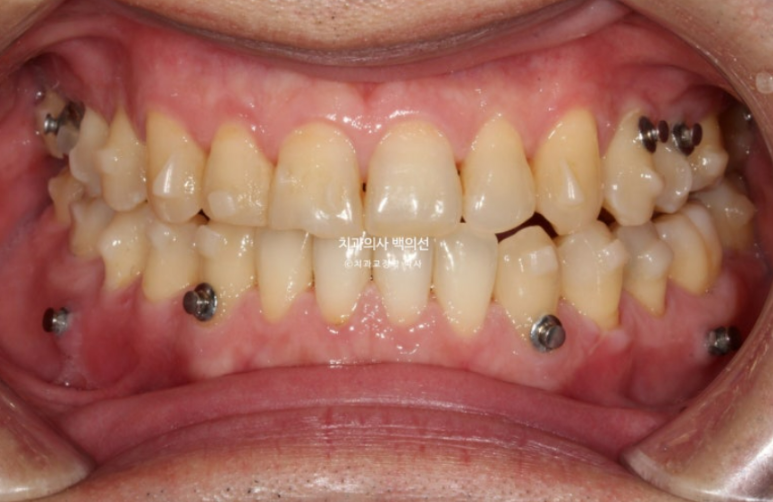

24.10

교정용 나사인 미니스크류를 아래쪽에 2개 심고 3급 고무줄을 걸며 치료를 진행중입니다.

치료시작 10개월차 첫세트의 장치를 모두 낀 후 모습입니다.

큰 공사는 끝났으나 미진한 부분들이 보입니다.

앞니 반대교합은 해결 되었으나 여전히 중심선이 미세하게 안 맞고

어금니 교합이 뜨는 부분이 있어 24년 10월 재제작에 들어갔습니다.